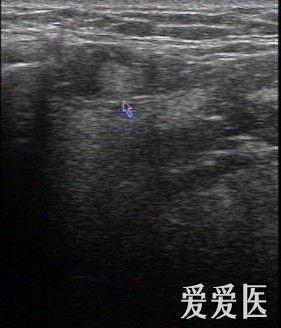

双侧颌下淋巴结肿大

双侧颌下淋巴结肿大,颌下淋巴结肿大

小儿2岁,发现双侧颌下无痛性淋巴结肿大1月余,请教下一步的最好方案是

颌下淋巴结肿大图片

小孩颌下淋巴结肿大图

两侧颌下淋巴肿大图片

颌下淋巴结有硬块图片